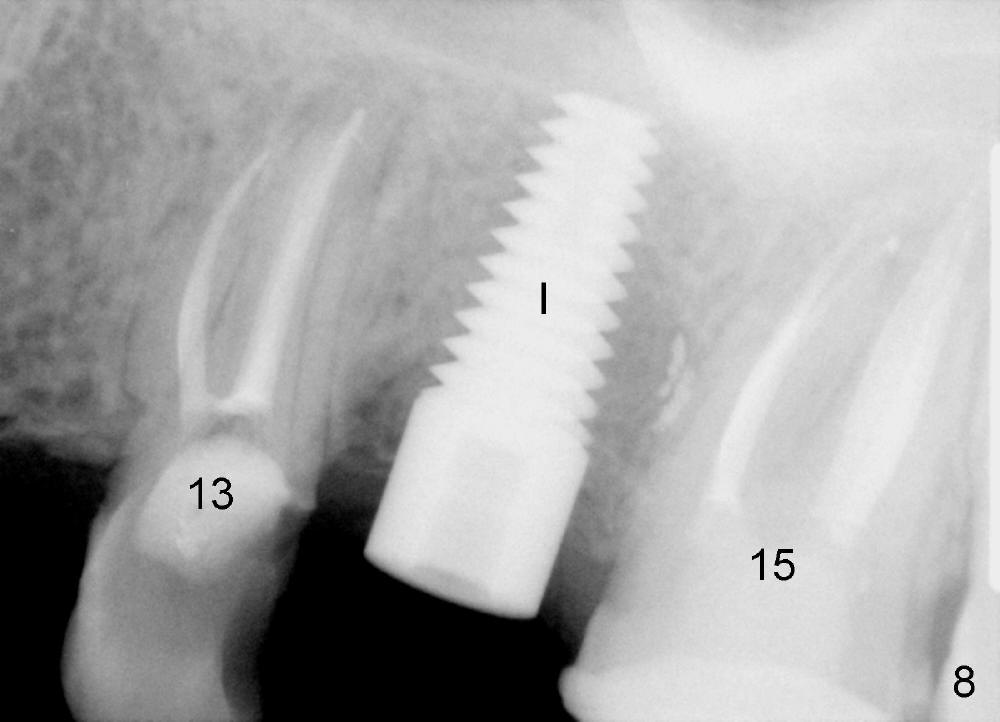

A 24-year-old man has poor dentition. The tooth #14 is beyond salvageable (Fig.1). The extraction socket is large (Fig.2). Dry socket develops 6 days post extraction without socket preservation (Fig.3).

The tooth #14 of a 79-year-old lady is also non salvageable (Fig.4), but this patient chooses immediate implant (Fig.5, 8x14 mm, no bone graft). The socket heals uneventfully (Fig.6, 2 weeks postop). The implant has been in function for 11 months.